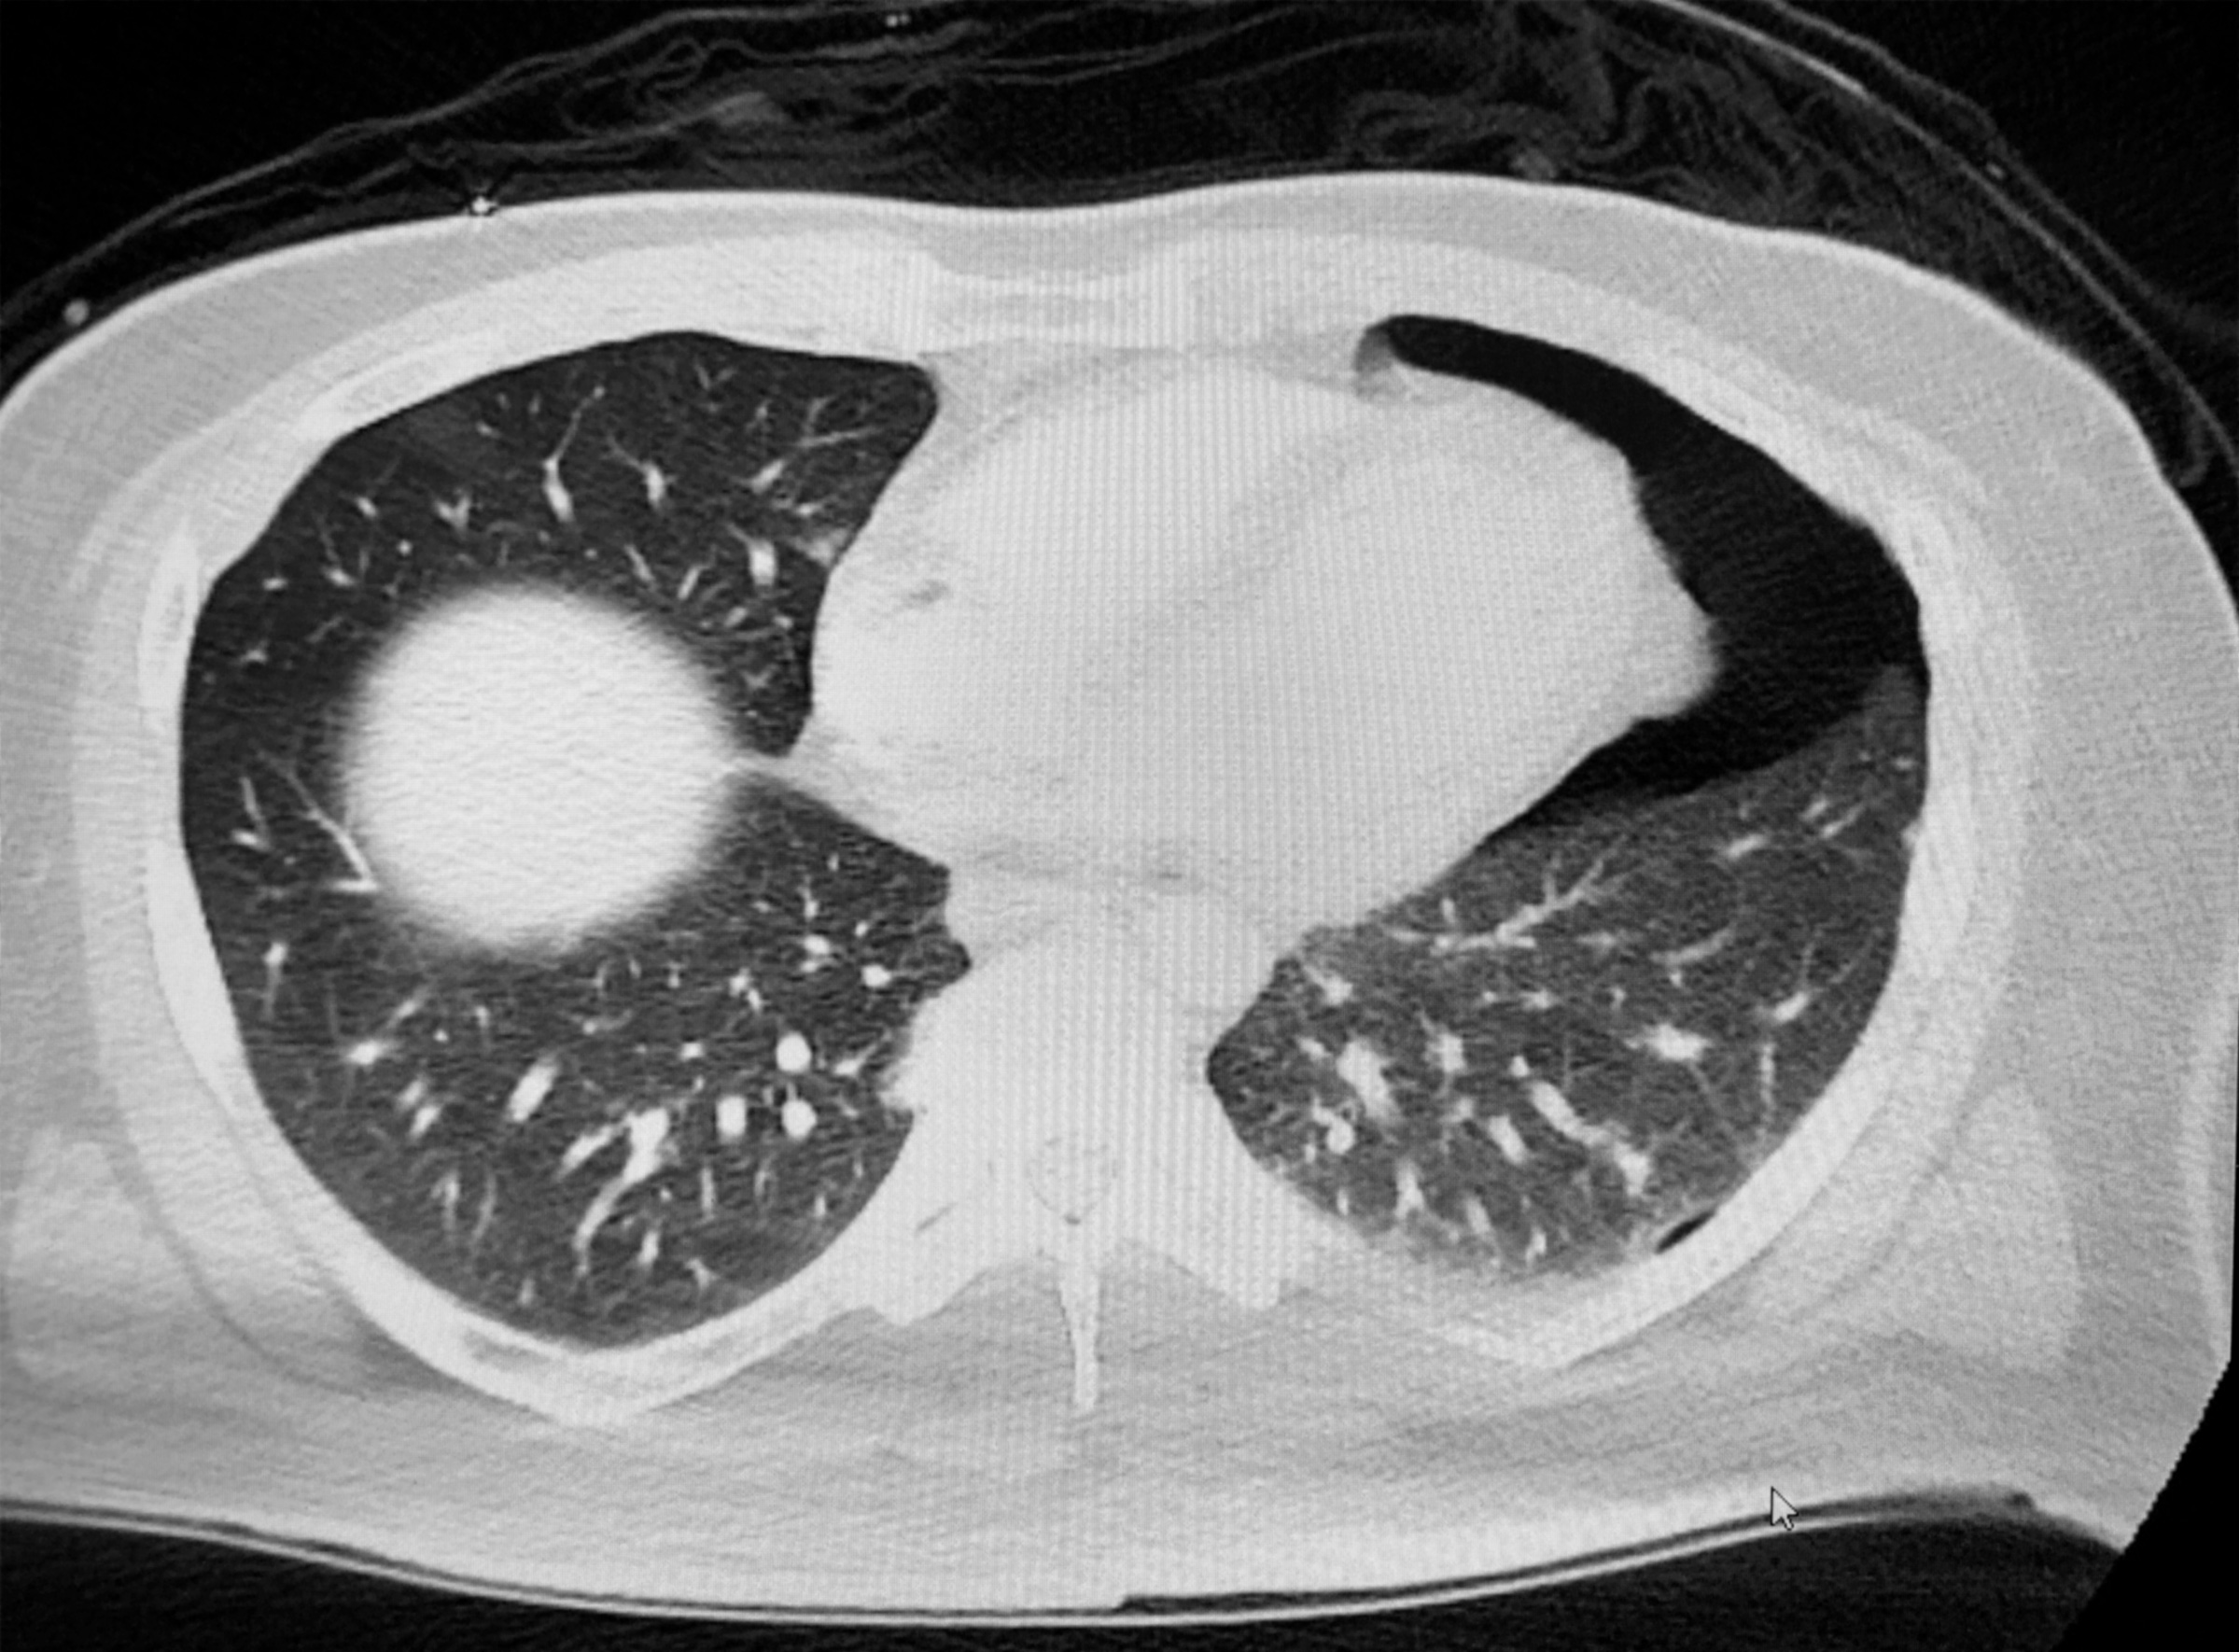

Прикроватное УЗИ сердца было выполнено в парастернальной проекцией по длинной оси, как показано ниже:

Имеется большой перикардиальный выпот с коллапсом правого желудочка во время систолы. Трудно сказать, есть ли коллапс во время диастолы из-за тахикардии у пациентки. Однако если вы остановите ультразвуковой клип и прокрутите его вперед и назад, чтобы найти момент, когда митральный клапан пациента открыт, вы видите, что сердце наполняется и, следовательно, находится в диастоле.

На кадре с видео синяя стрелка указывает на коллапс правого желудочка во время диастолы.

На этом кадре сердце показано в диастоле, а по стрелке видно прогибание правого желудочка. Некоторые говорят, что это похоже на прыжки на батуте. Диастолический коллапс правого желудочка является одним из определяющих признаков тампонады сердца. Для диагностики тампонады перикарда необходимо наличие перикардиального выпота (размер выпота не обязательно имеет значение) + диастолический коллапс правого предсердия ИЛИ диастолический коллапс правого желудочка. Диастолический коллапс правого предсердия является самым ранним признаком, но у пациента должен быть коллапс правого предсердия в течение по крайней мере 1/3 сердечного цикла, что может быть трудно определить с помощью УЗИ. Поэтому, обычно тампонаду диагностируют при диастолическом коллапсе правого желудочка.

Перикардиальный выпот у этой пациентки, вероятно, может быть подострым, учитывая размер и эхогенность выпота (свежая кровь анэхогенна и выглядит более изоэхогенной).